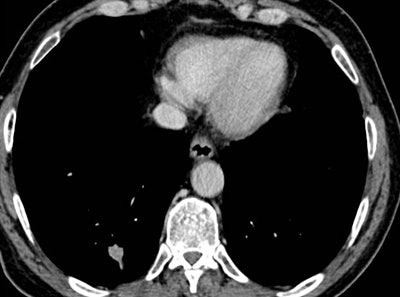

In her Liverpool talk, Strickland showed examples of missed lung cancers. In one case, leading to a duty of candour procedure, the lung bases, visible on a CT scan of the abdomen performed for suspected pancreatic pathology, had not been looked at on lung contrast windows, causing a small right basal lung cancer to be missed (see images above). On a subsequent chest CT scan several months later, the lesion was much bigger, and a second cancer was present in the left upper lobe. A duty of candour was issued because the lung cancer was at a higher stage when it was finally detected, likely leading to a worse outcome for the patient.

As we discussed in consultation this morning, I am very sorry that your CT scan undertaken to investigate pain in your abdomen and pancreas on Xth April 2014 did, in fact, show a small nodule in the bottom of the right lung. It is likely this was the early stage of the squamous cell cancer that we have now found in the right lung and are planning to treat.

A full and thorough investigation will be carried out by XXX Hospital as to why this small nodule was overlooked on the CT scan and why the scan was not flagged to the lung cancer team.

Again, I do apologize that this was missed, and I am very confident that we have a good plan for your treatment moving forward.